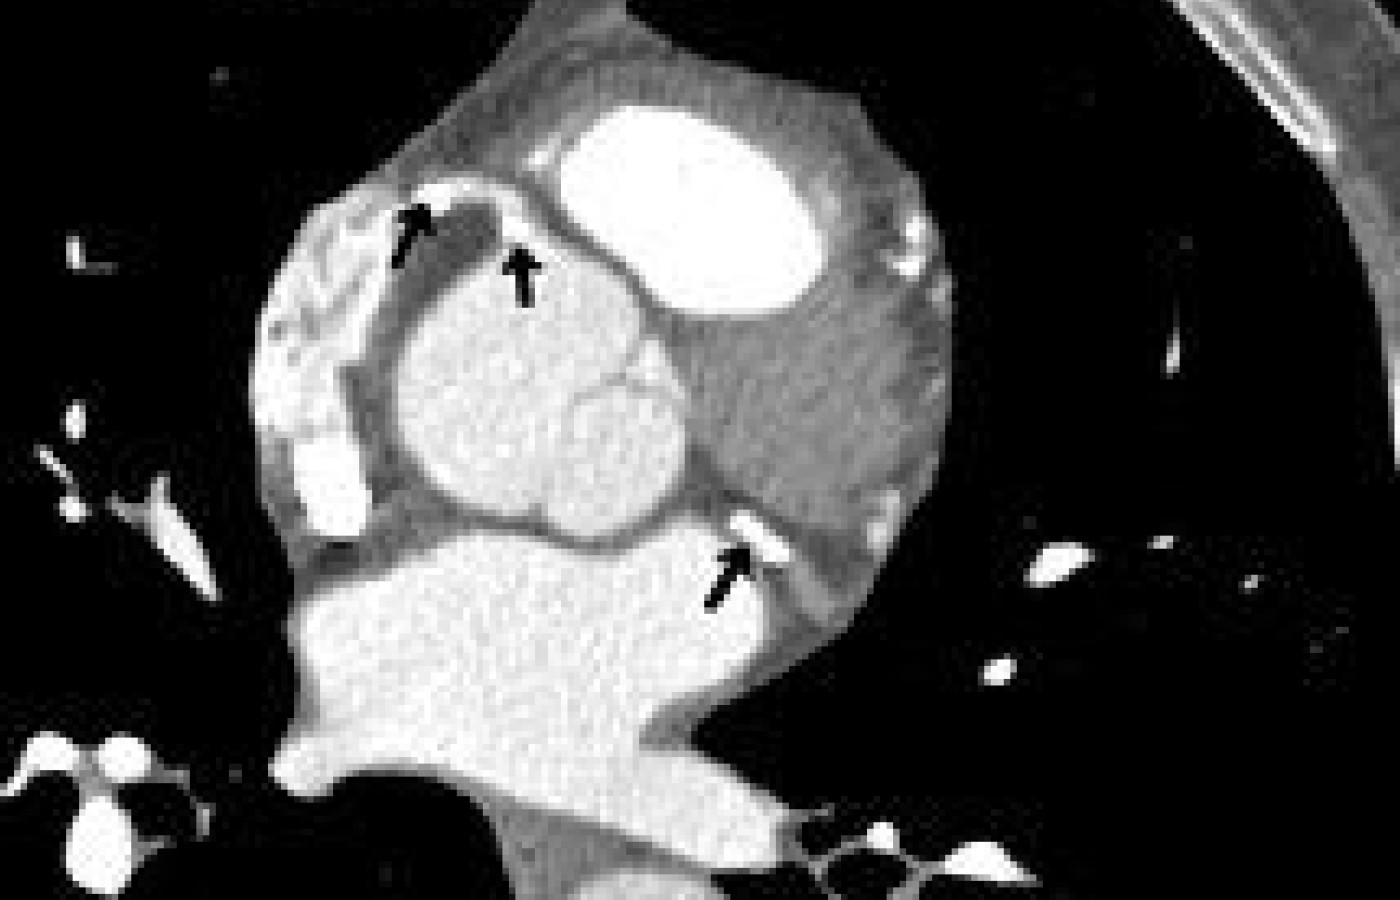

Cardiac CT is particularly useful for detecting high densities in the body; for example, calcium in vessels. Calcium scoring is a technique whereby the extent of calcification in the coronary arteries is measured and scored. It has been around for many years and was initially performed using electron-beam CT (EBCT). This technique is now increasingly performed using multi-slice CT, which is a faster scanner and is considered more accurate. Programs have been designed to identify Ca+ in lesions at a specific threshold, i.e., 130 Hu. The lesion score is calculated by multiplying the lesion area by a density factor derived from the Hounsfield unit (Hu) within this area. For example, a density factor of 1 is assigned for lesions with a maximal density of 130-199 Hu; a density factor of 2 for lesions 200-299 Hu; 3 for lesions 300-399 Hu; and a density factor of 4 for lesions > 400 Hu.

A total calcium score is derived by summing individual lesion scores from each of four anatomic sites (left main, left anterior descending, circumflex, and right coronary arteries). This calculation becomes the calcium score. There is a direct correlation between the extent of calcium in the coronary arteries and the risk of a future cardiac event (heart attack). For example, a calcium score of more than 400 is considered severe, and it would be necessary to take steps to prevent further advancement of atherosclerosis and plaque formation. The higher the calcium score, the more likely there is severe stenosis. On the other hand, a calcium score of 0 does not rule out the existence of soft plaques, but statistically rules out significant coronary artery disease. Though the calcium score does not allow us to evaluate the incidence of soft plaques, it does alert us to the presence and extent of CAD. The higher the calcium score, the more likely soft plaques are present. (Remember that the rupture of a soft plaque is the most common cause of acute coronary syndrome.)2